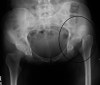

X-ray : 고관절 탈구(Hip posterior dislocation)

Pelvic AP, 무릎을 포함하여 Femur AP & lateral view 검사를 합니다. AP 사진상 정상골반에서는 대퇴골두의 관절간격의 크기가 대칭이며 같습니다.

뒤쪽 탈구시에는 손상 쪽 대퇴골두가 정상쪽으로 작아 보이며, 앞쪽 탈구시에는 손상 쪽이 더 큽니다. 절구 골절 동반도 흔하며(특히 뒤쪽벽), 이 경우 골절 유형 평가를 위해 CT 촬영을 합니다.